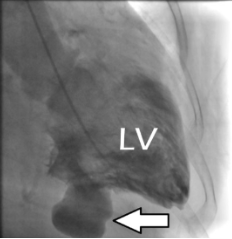

Ventriculografia: ao injetar contraste há a presença de extravasamento de contraste (seta branca):

Ventriculografia, evidenciando pseudoaneurisma.